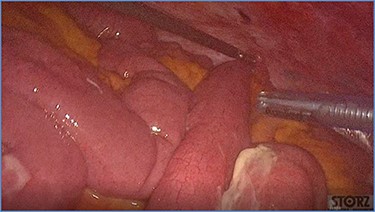

fluid collection in the peritoneal cavity. Subsequent CT confirmed the presence of diffuse fluid collection in the peritoneal cavity (Fig. 1) but no free air, with distention, bundling and thickening of some small bowel in the left quadrant (Fig. 2). The patient was therefore admitted for supporting therapy (intravenous fluids and antibiotics) with the suspicion of cocaine-induced small bowel ischemia. Twelve hours later, signs and symptoms of diffuse peritonitis developed: worsening diffuse abdominal pain with rebound guarding at examination, a significant increase in WBCs count (16.15 × 103/μl) and neutrophilia (88%), lengthening of coagulation times (INR: 1.68; aPTT: 33.0 s) and increase in fibrinogen (430 mg/dl) and D-Dimer (2275 ng/ml). Therefore, urgent surgical exploration of the abdomen through a three-port open laparoscopic approach was performed, confirming the presence of 1200 ml of exudative fluid and fibrin clots (Fig. 3). Several adhesions between greater omentum, abdominal wall and small bowel underwent blunt dissection. Thorough exploration of the small bowel revealed two ischemic segments located at about 50 and 100 cm from the Treitz ligament (Fig. 4). The large bowel appeared normal. The existence of non-visible gastro-duodenal perforations was ruled out with the administration of 500 ml of saline with 20 ml of methylene blue through the nasogastric tube. An iv bolus of sodium heparin, 10 000 IU, was then administered, performing a 30-min peritoneal lavage with 5 l of saline solution at 37°C. After reaspiration of peritoneal lavage, a new complete exploration of the small bowel was performed, showing complete revascularization of the two ischemic small bowel segments (Fig. 5). Two tubular drainage tubes were placed in the left and right colic gutters. Culture examination of peritoneal exudate was positive for multi-sensitive Escherichia coli and Enterococcus, thus confirming bacterial translocation peritonitis. Postoperative therapy included the administration of iv piperacillin–tazobactam and subcutaneous low molecular weight heparin. Postoperative recovery was smooth, with oral feeding on the second postoperative day (POD), drainage removal on POD 3, complete bowel function restored on POD 4 and home discharge on POD 5. At 15- and 30-day-follow-up, the patient showed full recovery, being now followed by a specialized support structure for his drug abuse.

Dilated small bowel loops at laparoscopic exploration: bowel ischemia is evident from the absence of visible vasa recta compared to the adjacent loops (a) 50 cm and (b) 100 cm from the ligament of Treitz.

Progressive small bowel revascularization perceived by slow reappearance of vasa recta after peritoneal lavage.